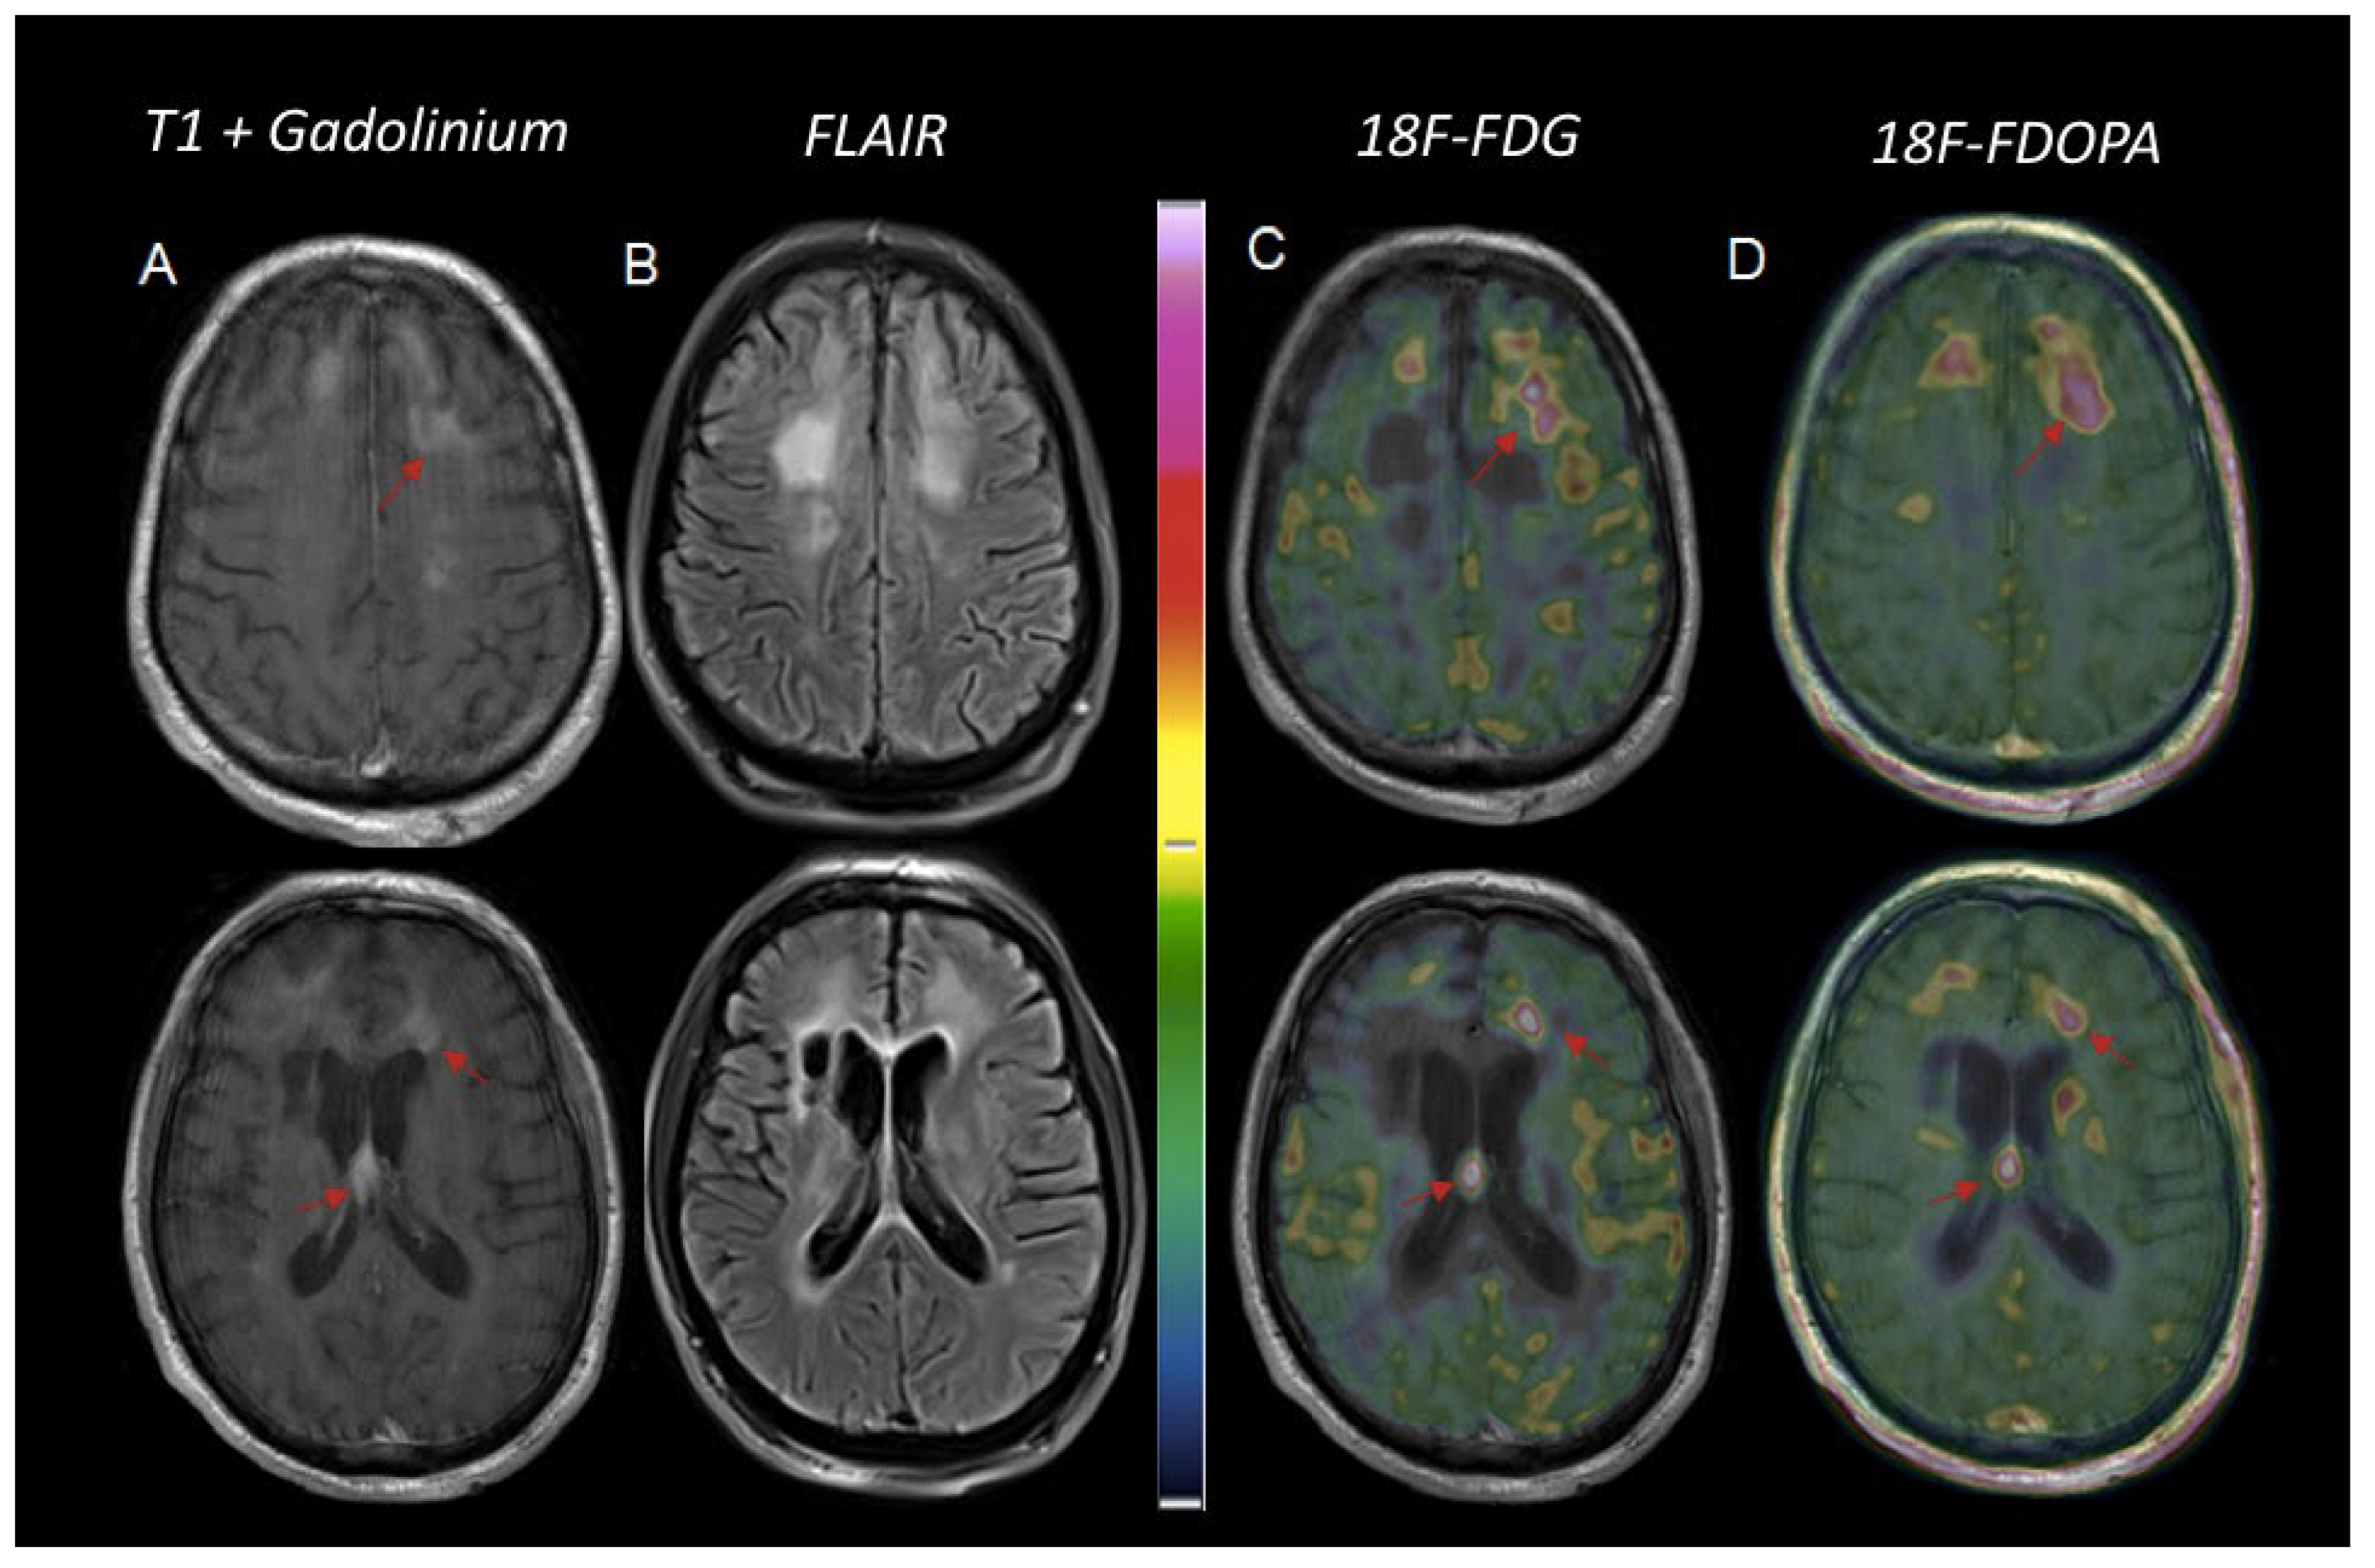

4. Others PET Tracers in PCNSL

5. Conclusions